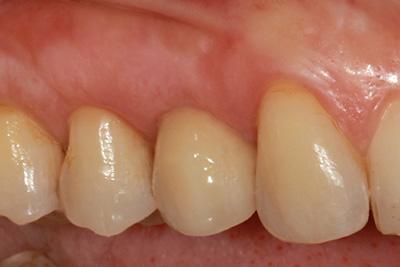

Completed crown and bridgework on implants